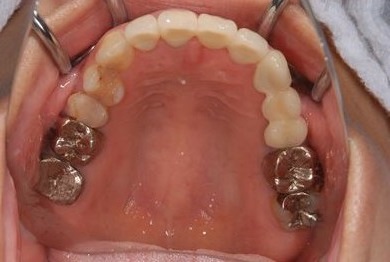

セラミックの症例写真 SHINBI

セラミック治療

| 主訴 | 前歯のさし歯の部分が目立ってしまい、新しくしたい。痛みも少しある。 | ||||||||||||||||||||||||||||||||

| 治療方針 | 保存不能な歯を抜歯し、セラミック治療にて、機能的・審美的回復を行う。 | ||||||||||||||||||||||||||||||||

| 治療内容 | ジルコニアフレームオールセラミッククラウン7本(オールセラミック用土台3本)、ハイブリッドセラミッククラウン1本、ハイブリッドセラミックインレー1本 | ||||||||||||||||||||||||||||||||

| 総治療費 | 1,390,305円 | ||||||||||||||||||||||||||||||||

| 治療期間 | 11ヶ月 |